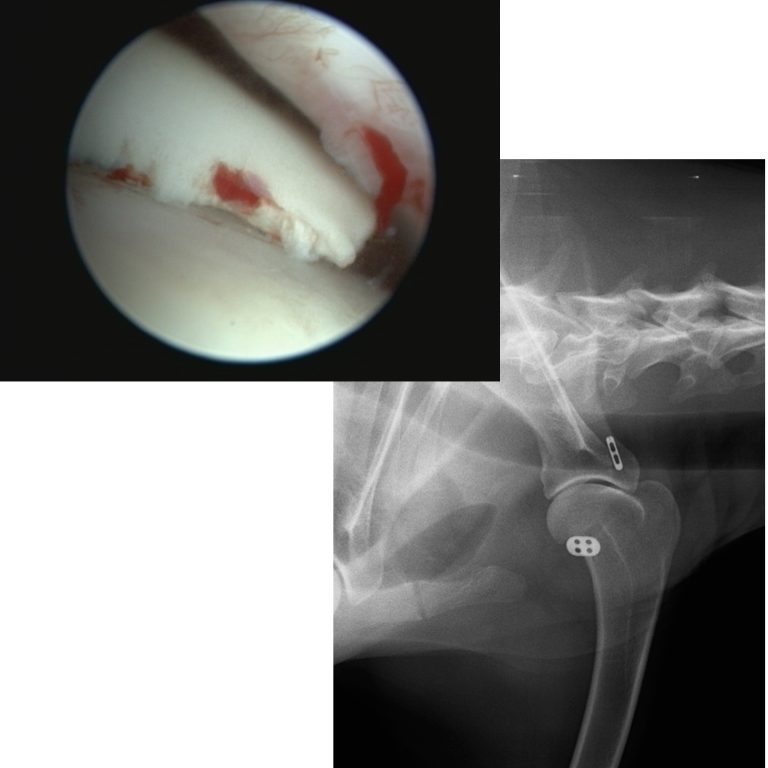

Curso de cirugía de rodilla

Abarca el diagnóstico y el tratamiento de la ruptura del ligamento cruzado craneal y la luxación de la rótula, incluida la artroscopia.

✓Artroscopia de rodilla ✓Luxación de rótula: TTT y DFO

✓TPLO, mTPLO y ortesis interna (Internal brace)